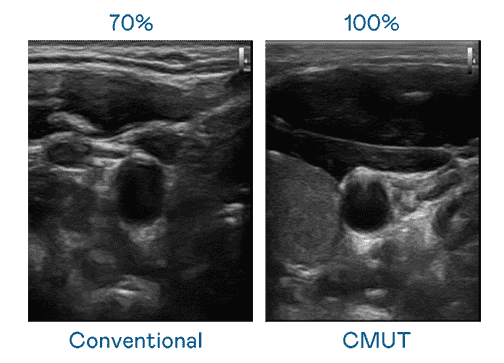

CMUT 技术是一种用电容式微机电元件来产生超音波讯号的技术。。。。与传统 PZT 压电式技术相比,,,CMUT 频宽增加 30%,,更宽频的超音波讯号让影像解析度大幅提升,,,,是实现高影像品质医疗超音波扫描、、、促进精准医疗发展的关键技术。。。

大频宽带来超清晰影像

超音波影像的解析度高低,,,,首先取决于探头能发出的讯号频宽。。。。尊龙集团 CMUT 可提供高清晰的超音波讯号,,,提供高频宽、、、高灵敏度、、、影像纹理细节更高的超音波影像,,,,协助医护人员缩短影像判读时间及利用精准的医疗影像进行诊断。。。